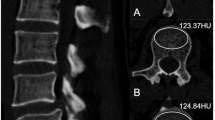

Analysis was performed on chest CT scans acquired on Acquillion One Genesis Edition (Canon Medical Systems, Otawara, Tochiqi, Japan). Contrast enhanced and non contrast enhanced CT images were acquired using a tube peak potential (KVp) of 100 and 120 KVp, respectively. The table feed was 32.5 mm per rotation (320 slice scanner with 80 × 0.5 mm collimation) with a spiral pitch factor of 0.813 and revolution time of 0.275 s using a 512 × 512 matrix. Reconstruction was performed using Adaptive Iterative Dose Reduction (AIDR3D) using an FC30 convolution kernel. CT scans were analyzed using the IDS7 viewer (version 25.3, Sectra, AB, Linköping, Sweden). Images were presented using a bone window (W:1800 L:400). Density of the vertebral body at the level of Th12 was assessed following the method as described by Pickhardt et al.12. In brief, a circular region of interest (ROI) was placed in the trabecular bone of the vertebral body stretching from the anterior part of the vertebral body (excluding cortical bone) and the basivertebral vein. One ROI for each scan was placed, in the axial image. Mean CT density (HU) was measured (Fig. 1). When placing the ROI, areas that would distort the CT density measurement (such as focal lesions, the internal posterior venous plexus or imaging-related artifacts) were avoided. Images with a slice thickness of 1.0 mm were used for analysis. Details on the assessment of bone density of Th12 is given in the Supplementary Materials. Density measurements were performed independently by three observers (EJ, DW, and NF; all intensive care physicians with varying levels of experience ranging from two to forty years) and mean values of the three observers were used for analysis. In some of the included patients, both contrast enhanced and non contrast enhanced CT images were obtained. If available, non contrast enhanced CT images were used for the main analysis. In additional analyses, we compared bone density between non contrast enhanced an contrast enhanced CT images, since venous enhancement could potentially influence measurement of CT density. For this comparison, the same ROIs were used (same size and location).

Measurement of CT-based bone density by manually placed ROI. CT-based bone density was measured by first locating the Th12 vertebral body in the sagittal plane (A). Subsequently, in the axial plane, a circular region of interest (ROI) was placed stretching from the anterior aspect of the vertebral body to the anterior side of the basivertebral vein (B). The mean CT-based bone density within the ROI was determined using the IDS7 software.